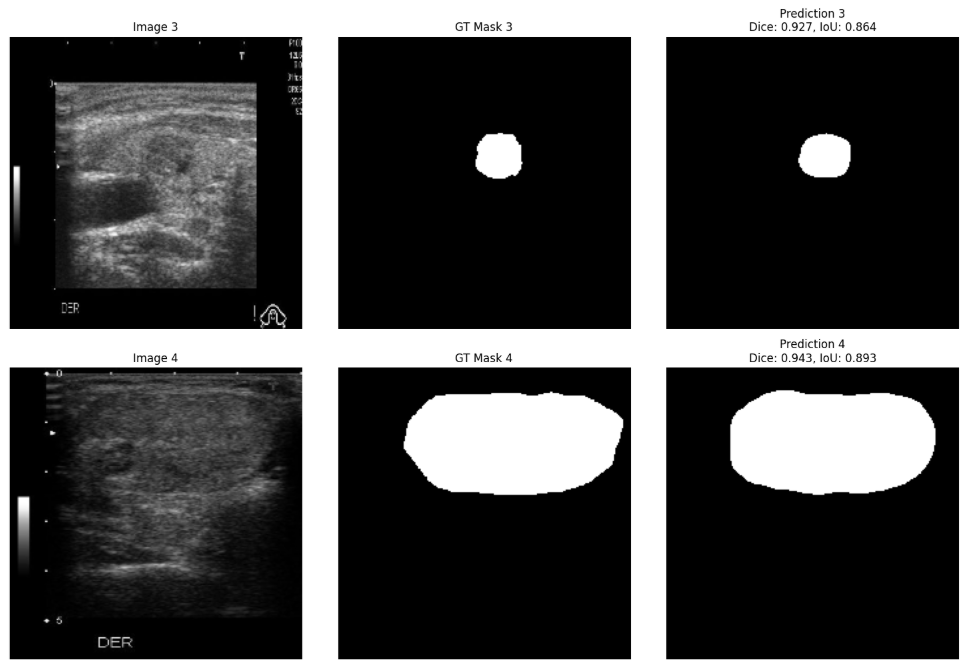

Based on these findings, we selected the TransUNet model trained on the combined dataset for subsequent classification. When evaluated on the DDTI test set (the cohort used for classification), this model achieved a Dice Score of 0.8624 and an Intersection over Union (IoU) of 0.7639. This high level of accuracy ensured that the masks provided a reliable basis for subsequent ROI extraction. Qualitative examples of segmentation outputs are shown in Fig. 2.

Refer to caption

Fig. 2: Qualitative segmentation results from the proposed model. Each row shows a different thyroid nodule example with three panels: (left) the original ultrasound image, (middle) the ground truth mask annotated by a radiologist, and (right) the predicted mask generated by the model.